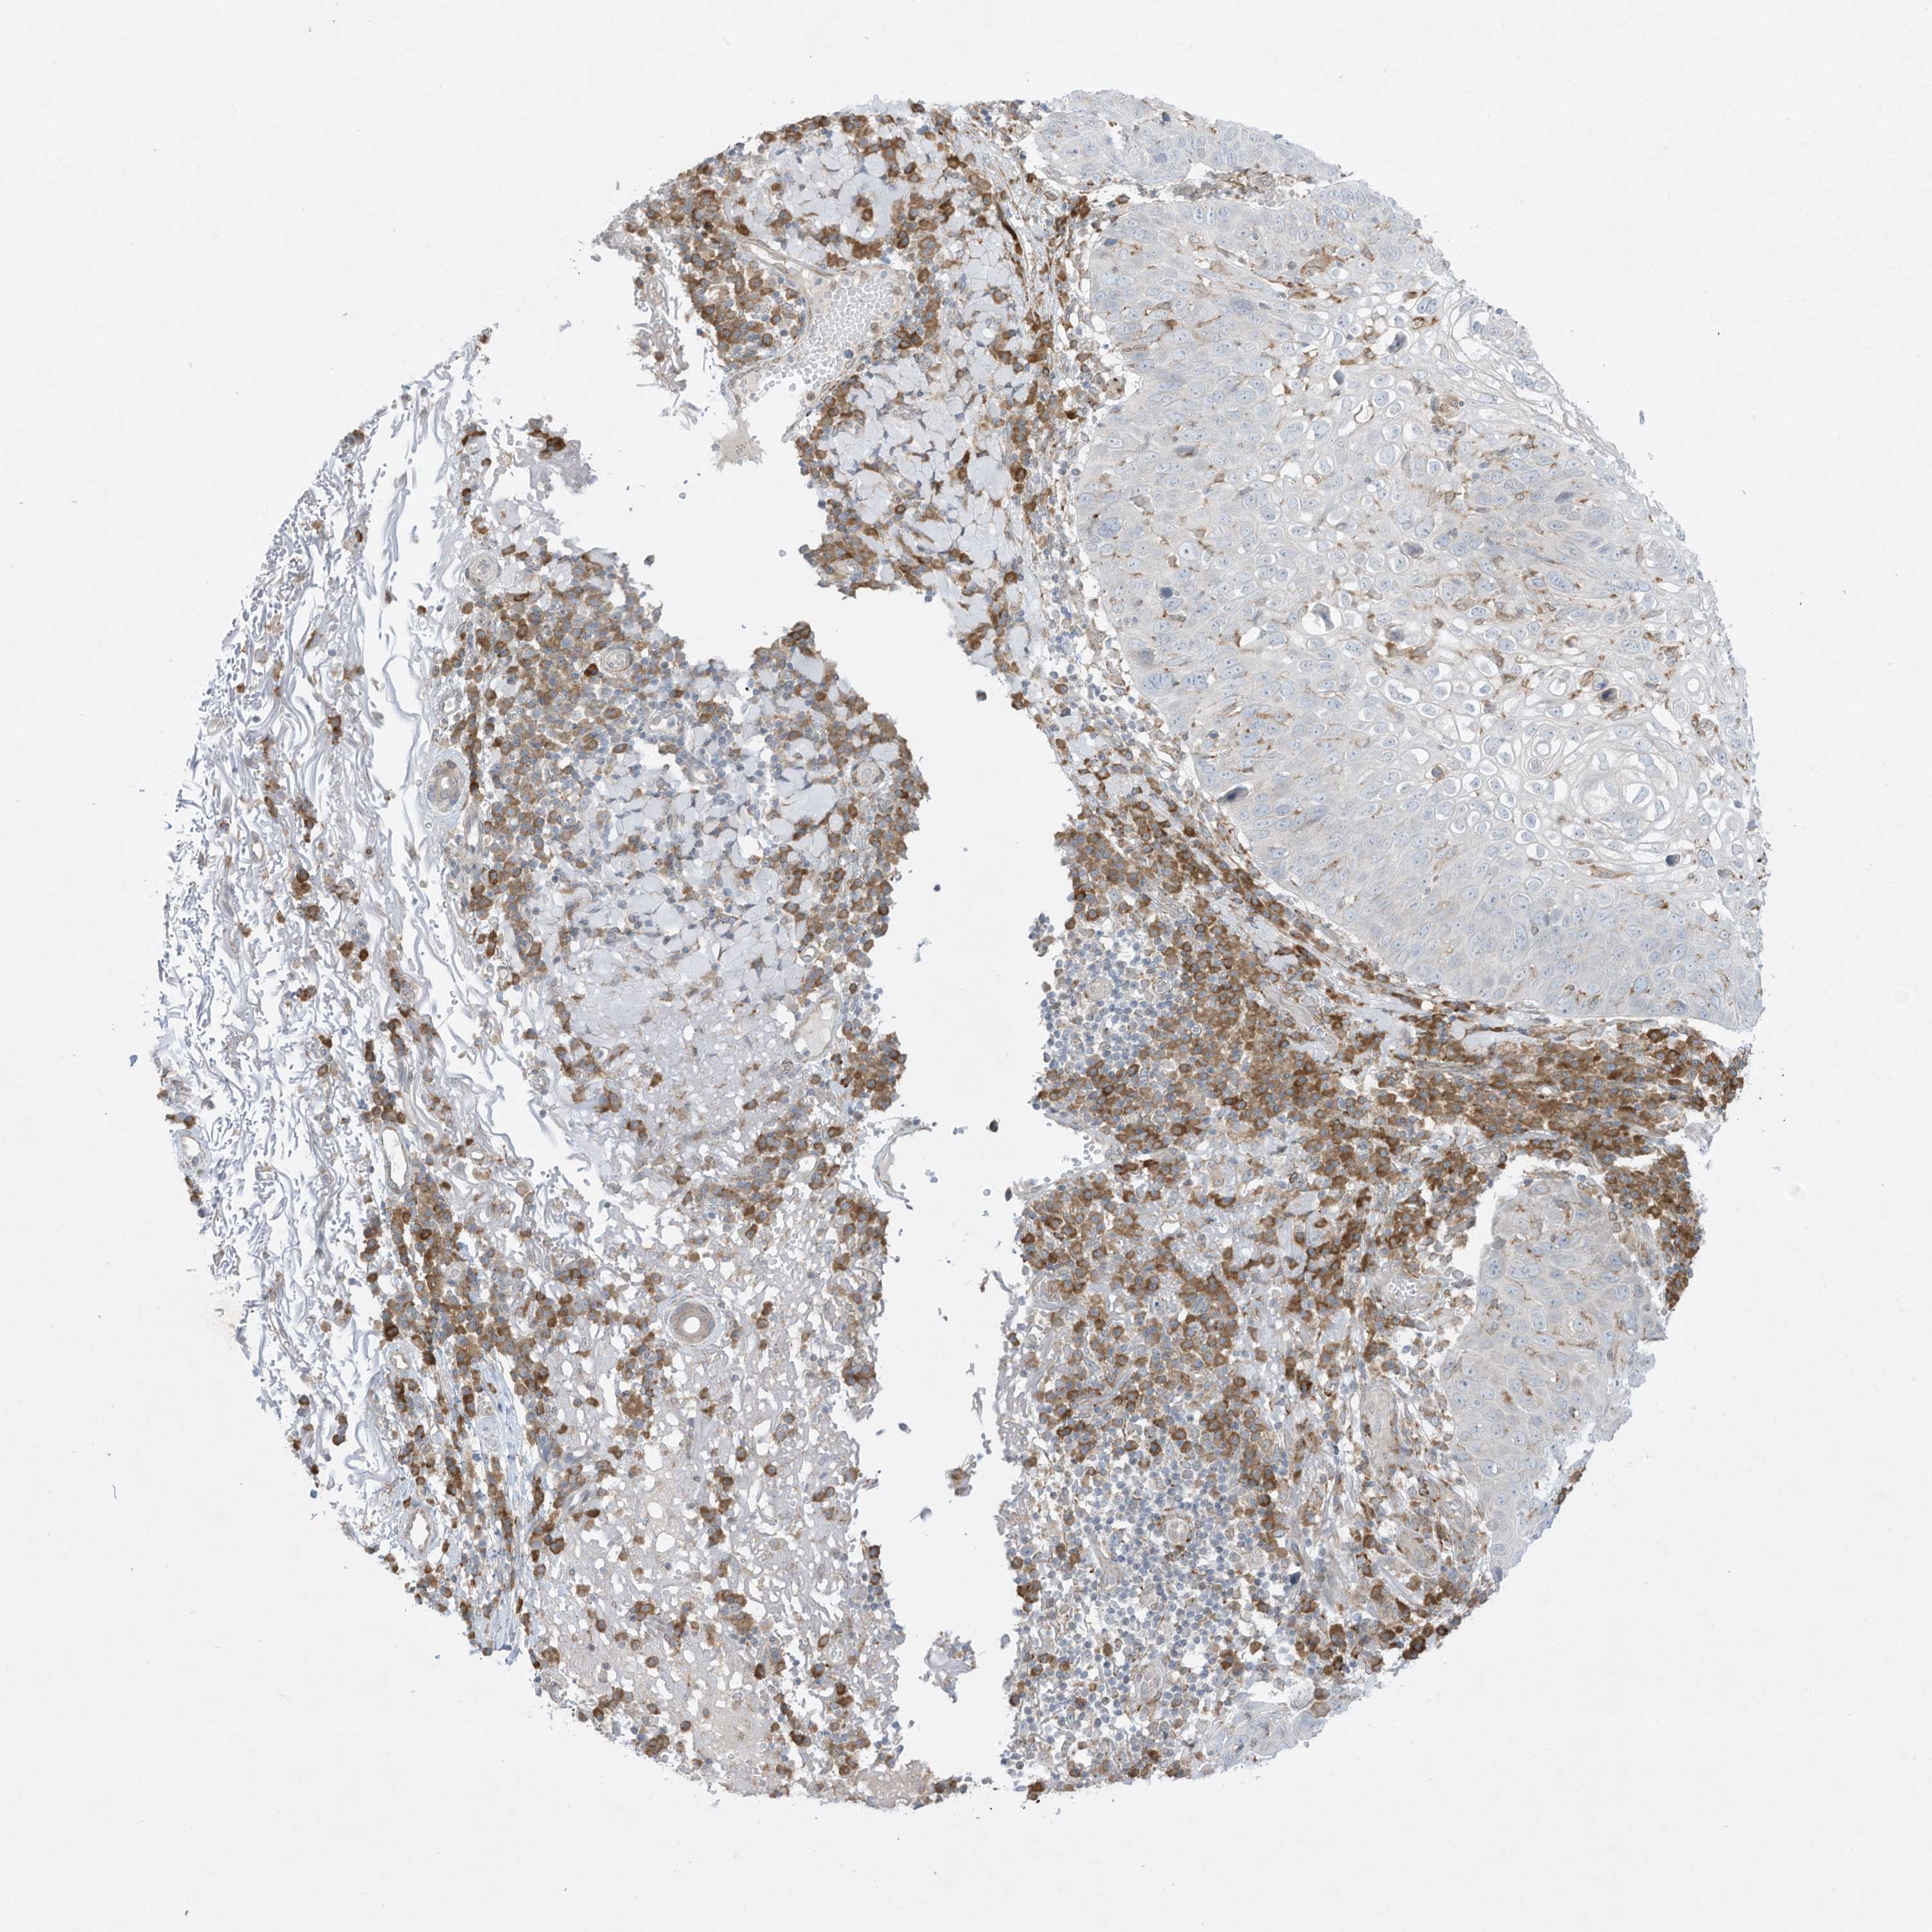

SKIN CANCER - Protein expressioni

A mouse-over function shows sample information and annotation data. Click on an image to view it in a full screen mode. Samples can be filtered based on level of antibody staining by selecting one or several of the following categories: high, medium, low and not detected. The assay and annotation is described here.

Each image is clickable and will lead to virtual microscopy that enables deeper exploration of all samples and also displays staining intensity scores, fraction scores and subcellular localization as well as patient and tissue information for each sample.

Antibody HPA036070

Basal cell carcinoma